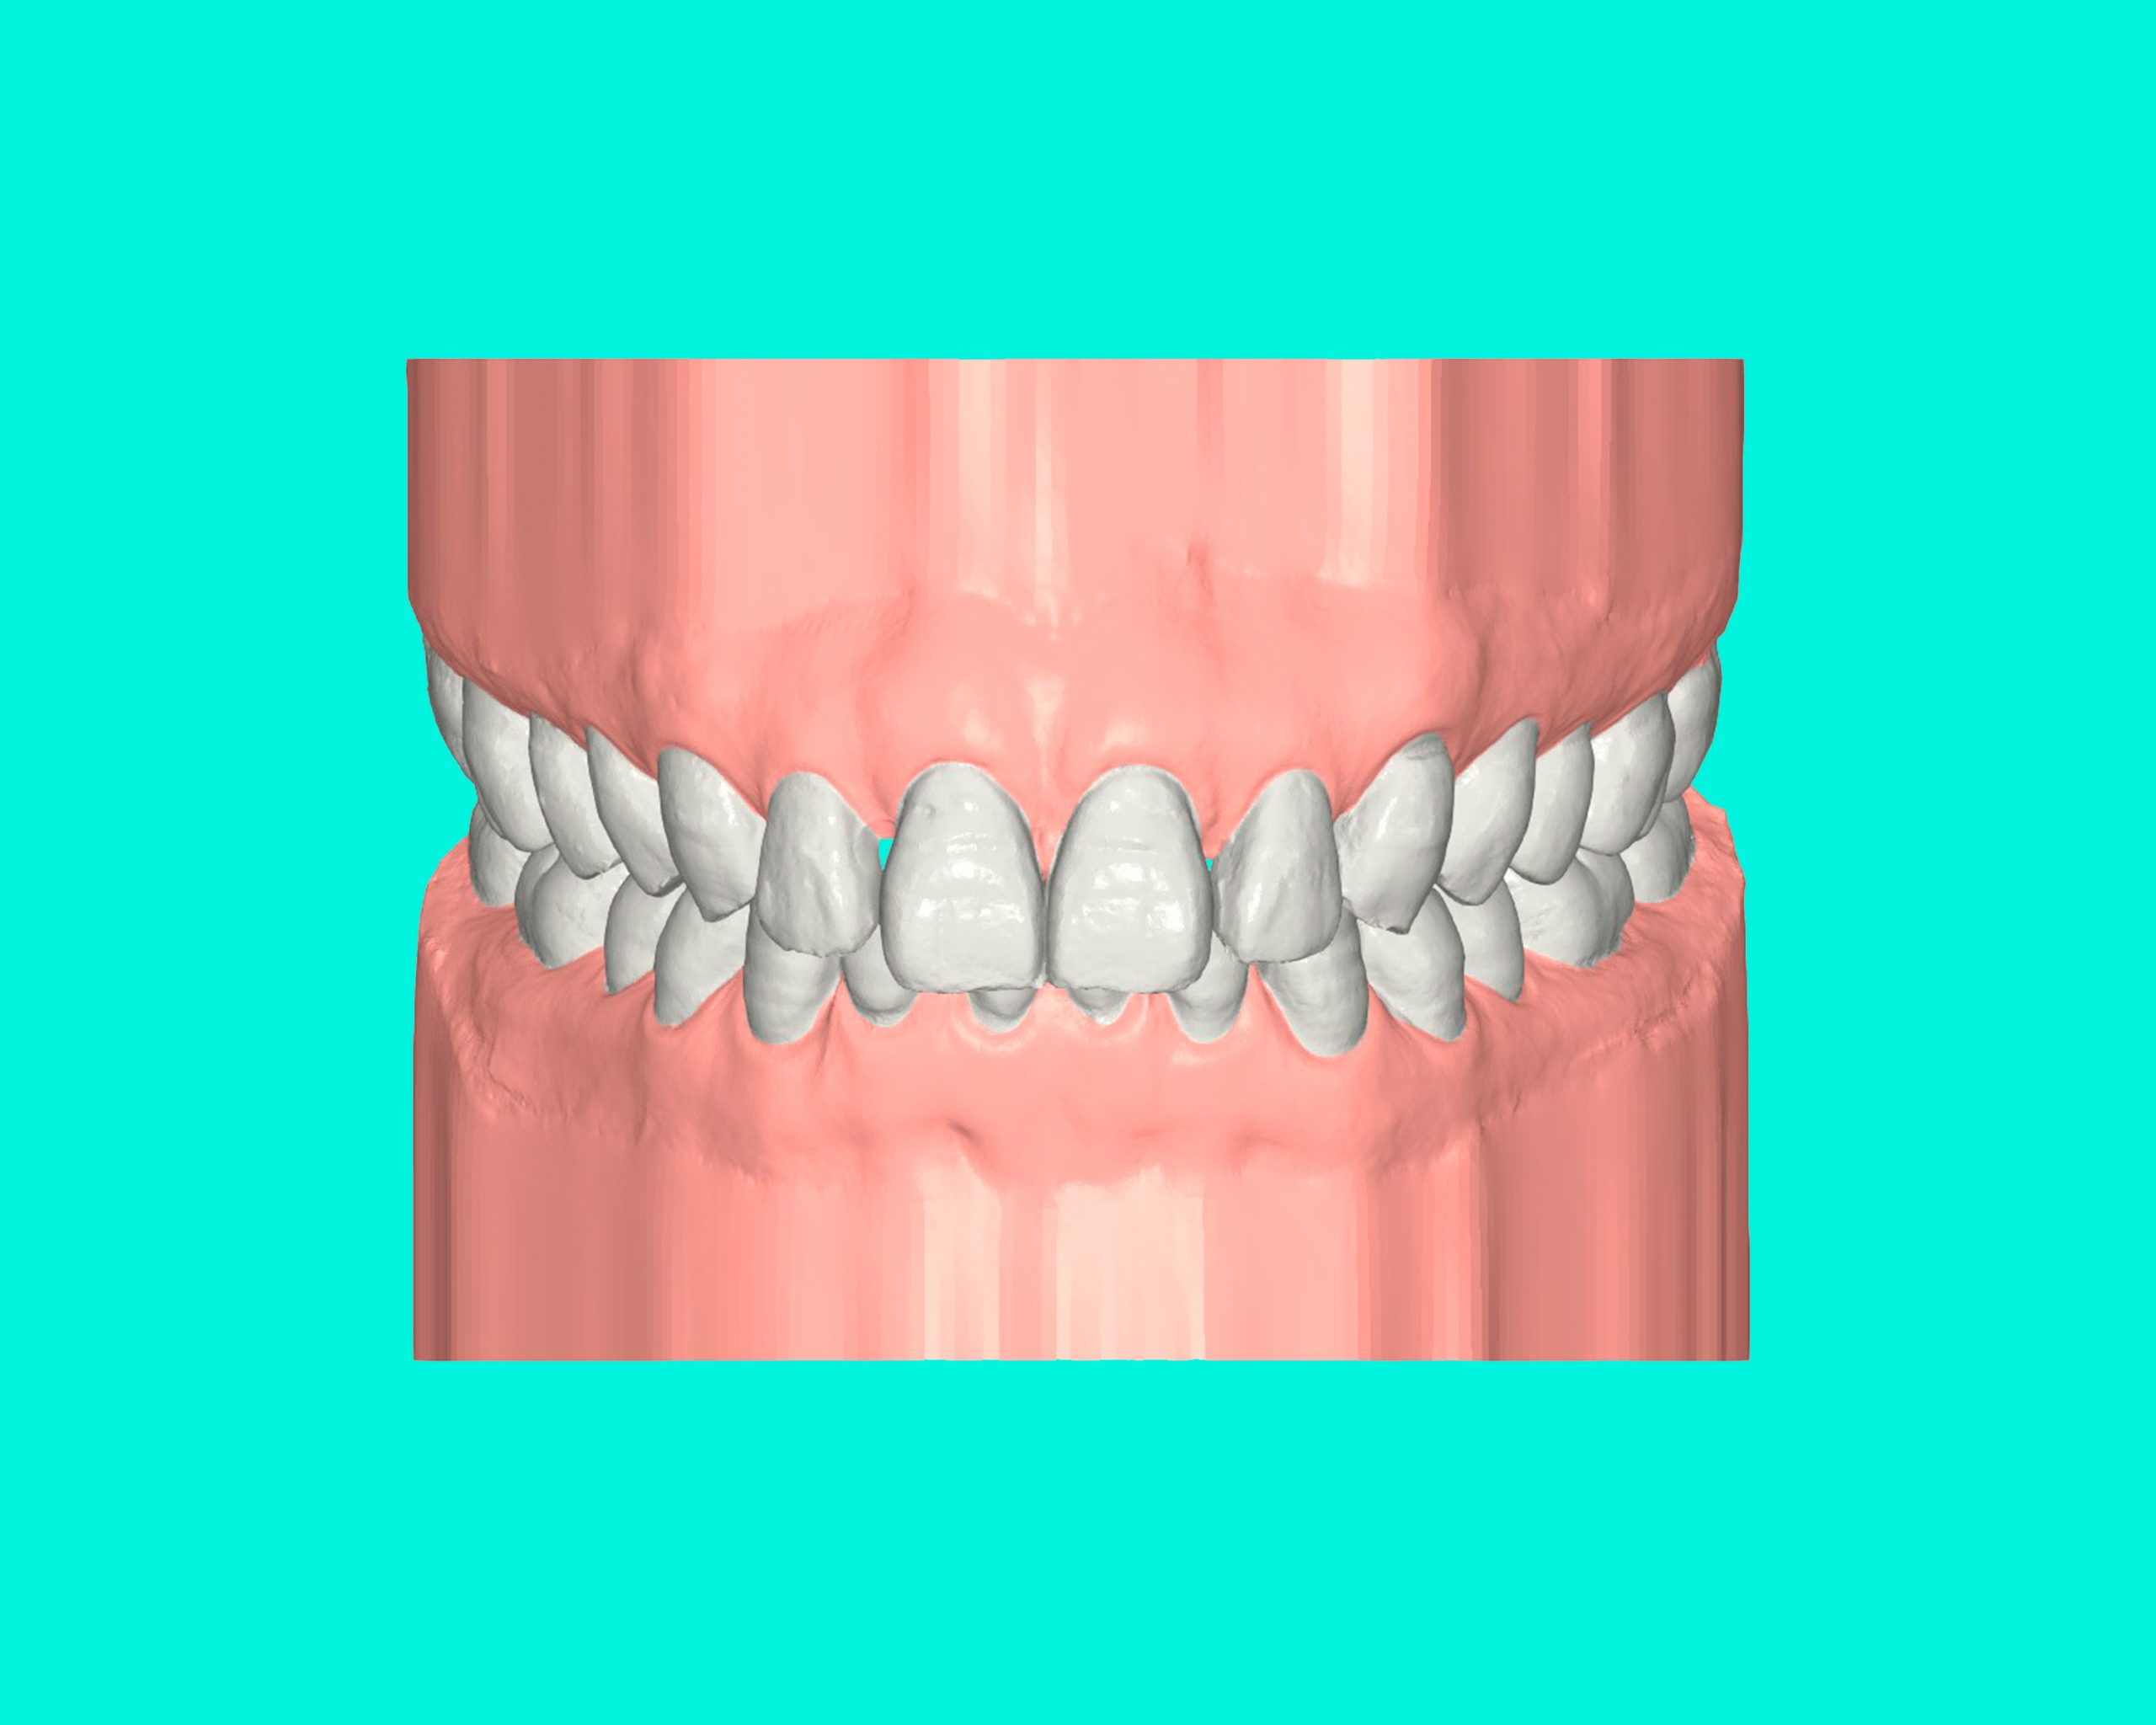

Maloclusión Clase III

La maloclusión dental de clase III se presenta cuando los dientes inferiores están más adelantados que los superiores, lo que provoca una sobremordida invertida.

Esta condición puede generar problemas en la mordida, dificultad para masticar y afectar la estética facial, especialmente en la proyección de la mandíbula.

FULL

35 Semanas de tratamiento